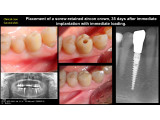

Clinical case in 2 VISITS: Direct dental implant placement, minimum trauma and maximum aesthetics. Permanent crown for the installed implant 35 days after implantation.

Dentist: DDS, PhD, prof MUSHAYEV ILIA, Sidhe Dent, Holon/Israel

Clinical case, dental implantation, dental surgery